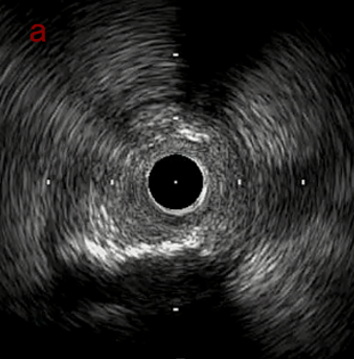

IVUS after OAS high speed 3回追加

IVUS imaging after high speed 3回追加

a,b,cの十分な石灰化のsanding。

High riskのbias所見へと変わっていったdの部位に関してはpinpoint OASを行うことでinjuryなく治療できた。

Cutting + DCBの方針に。